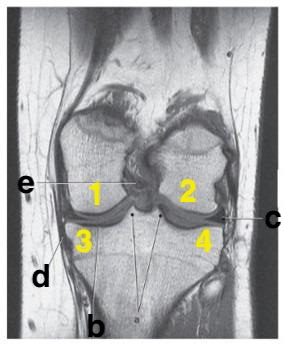

What is letter b?

Medial meniscus

What structure cushions the articulation between the femoral condyles and the tibial plateaus?

Menisci

What is letter d?

posterior cruciate ligament

What is # 4?

Which letter is pointing to the posterior cruciate ligament?

e

Number 2 is on the __________ side of the patient.

lateral

Which letter is pointing to the patellar ligament?

b

medial collateral ligament

Which letter is pointing to the anterior cruciate ligament?

c

Where is the tibial plateau?

3 and 4